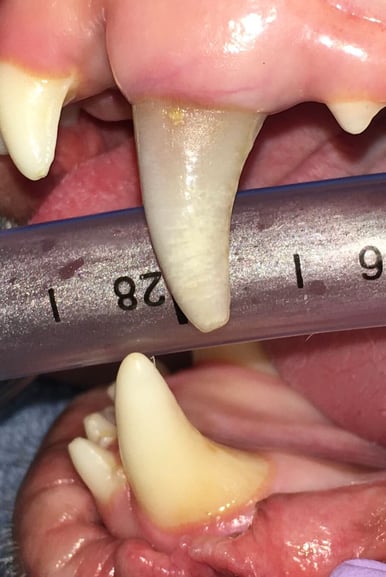

A root canal procedure was performed on tooth 204, which was non-vital. To access the pulp chamber, a round surgical length bur was utilized. Upon reaching the pulp chamber, a radiograph was taken to ensure cleaning at the working length, which in this case was 38mm. Cleaning and shaping of the canal were carried out using Dentsply NiTi and LightSpeed files in alternation with suction aided sterile saline and sodium hypochlorite solutions.

Below: During RCT - Radiograph finding working length to clean and measure canal

%20-%20March%202024/during%20RCT%20-%20finding%20working%20length.jpg?width=379&height=291&name=during%20RCT%20-%20finding%20working%20length.jpg)

Below: During RCT - finding master file size to clean canal walls appropriately and find master cone size of gutta percha

%20-%20March%202024/Radiograph%20of%20master%20file%20during%20RCT.jpg?width=386&height=296&name=Radiograph%20of%20master%20file%20during%20RCT.jpg)

Below: After cleaning, a gutta-percha point was sized to aid in filling, with radiographic confirmation of reaching the tip.

%20-%20March%202024/Radiograph%20of%20dry%20fit%20of%20gutta%20percha%20during%20RCT.jpg?width=386&height=297&name=Radiograph%20of%20dry%20fit%20of%20gutta%20percha%20during%20RCT.jpg)

The test size was then removed, and the canal was filled with a liquid version of gutta percha, pressing in the solid gutta-percha point to the working length. Excess gutta-percha was trimmed and the walls cleaned using special techniques.